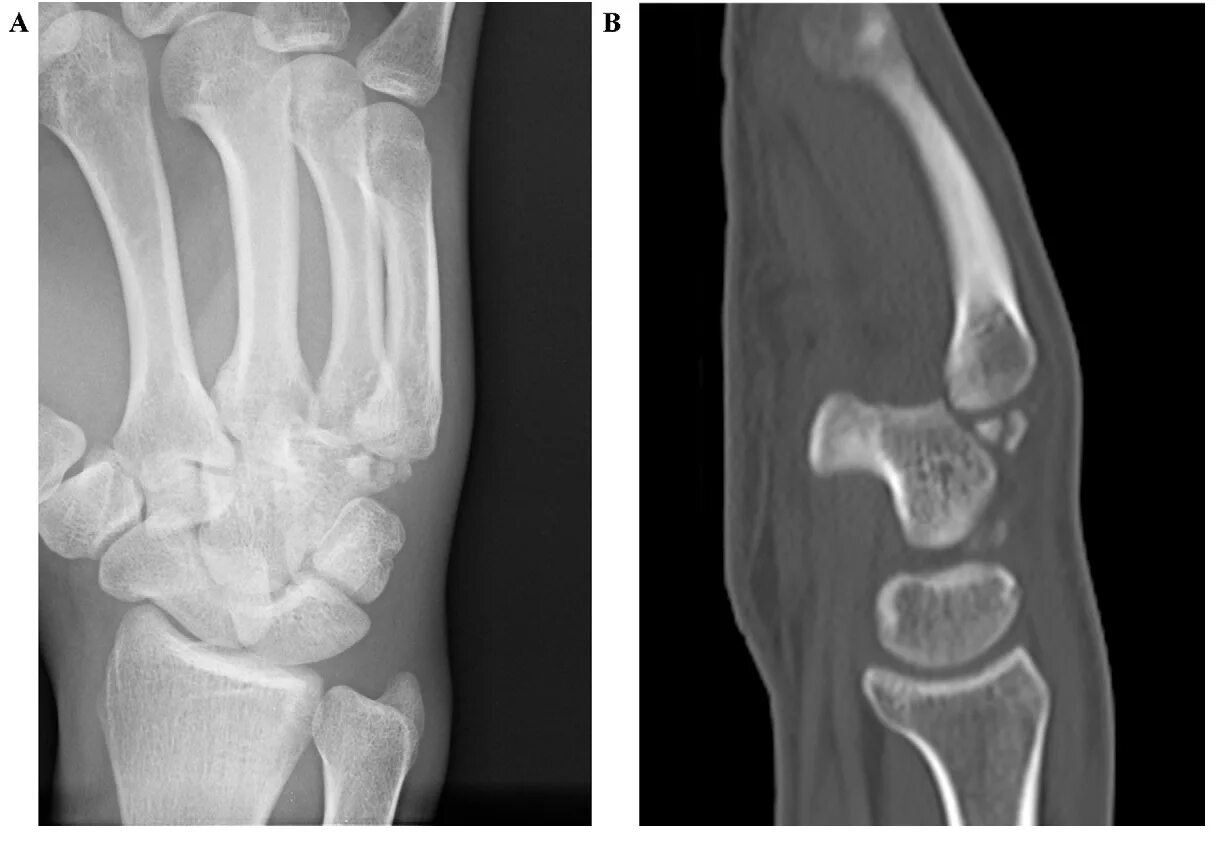

Перелом 3 пястной кости